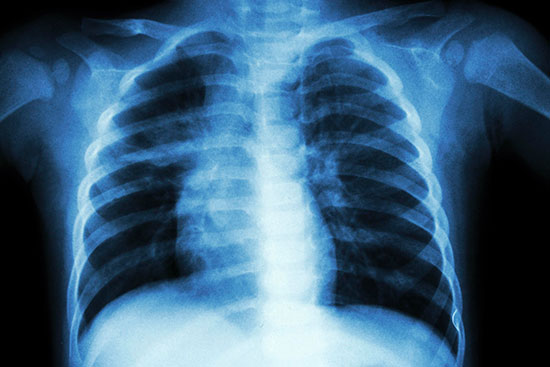

Melbourne merkezli Peter MacCallum Kanser Merkezi, akciğer kanseri tanıları için IBM Watson’ı kullandıklarını açıkladı.

Çalışmada 102 akciğer kanseri hastasının geçmiş kayıtları kullanıldı. Klinik araştırmaların eşleştirilmesi için kullanılan IBM Watson, her bir hastayı 10 potansiyel kayıtla eşleştirdi ve normalde saatler alan manuel klinisyen eşleşmesine kıyasla yüzde 92 doğruluk elde etti.

Bununla birlikte IBM Watson, klinik çalışma uygunluğu açısından hastaları taramak için gereken süreyi yüzde 78 oranında azalttı.